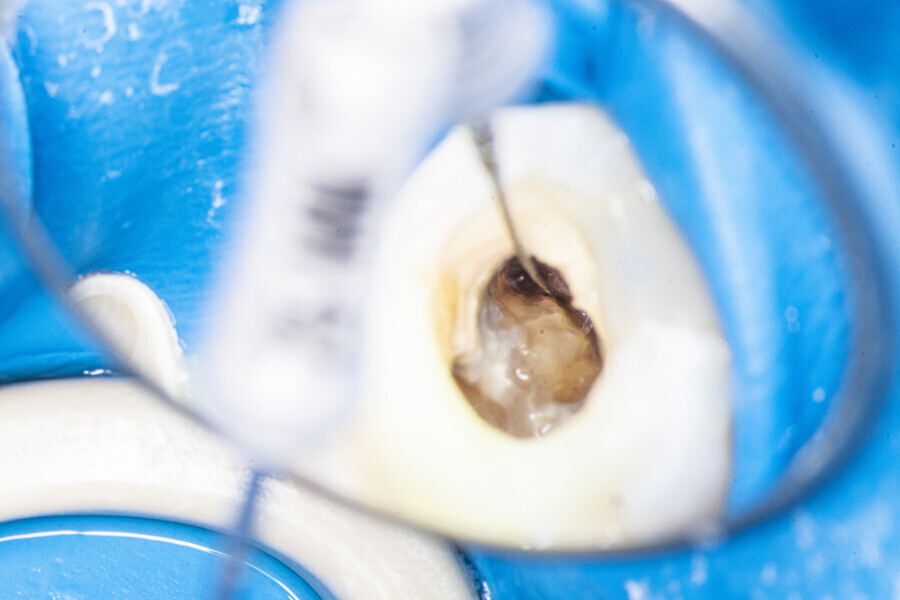

The first trials of the LPE concept were performed on extracted human molars. Although the dynamics of fluid during root canal irrigation are completely different in vivo than in extracted teeth, these kinds of trials provide initial information about the procedure. Some of these teeth had apices closed with a coat of wax and composite resin to close the apical delta and simulate the periapical tissue. After creation of the access cavity, the pulp chamber was cleaned with continuous irrigation with 5.25% NaClO activated with a SkyPulse laser (Fotona) in AutoSWEEPS mode (20 Hz, 15 mJ). A 25/0.07 reciprocating file (Shenzhen Perfect Medical Instruments) was used to perform the pre-flaring procedure. After opening the coronal third, continuous irrigation with 5.25% NaClO activated with the laser was used to clear the debris for 30 seconds. After removing the debris, a #10 C-PILOT file (VDW) was used to establish apical patency, without forcing the file if possible. In some cases, apical patency was reached already at this stage of root canal preparation. In all cases, the second step of instrumentation was the preparation of the middle third with the same file, and the same irrigation procedure was performed. Subsequently, the C-PILOT file was used to reach the apical foramen. At this stage, apical patency was reached in most cases, but in some roots, there was no possibility of entering the apical foramen. The working length was confirmed with a radiograph with the hand file. Usually, the next procedure to be done is apical preparation, but the LPE concept is based on an enhanced irrigation protocol. Following this protocol, irrigation was performed for 5 minutes with continuous flow of 5.25% NaClO activated with the SkyPulse laser in AutoSWEEPS mode (20 Hz, 20 mJ) with a conical sapphire fibre. The next step was alternating irrigation with 17% EDTA for 30 seconds, with 5.25% NaClO for 30 seconds and with 17% EDTA for 30 seconds, all activated with AutoSWEEPS, followed by irrigation for another 5 minutes with 5.25% NaClO activated with AutoSWEEPS. In most cases, the next step after this stage of enhanced irrigation was the calibration of the apical constriction rather than apical preparation per se, but this step requires further investigation.

At the first appointment, both teeth were opened, the old restorations were removed, all the root canal orifices were located and the first mesiobuccal (MB1), distobuccal (DB) and palatal canals were shaped. In both teeth, the MB2 orifices were located, but the canals were not shaped. The preparation phase was similar to that explained earlier. During the root canal preparation phase, the hand file was used to establish patency after each reciprocating instrument, and the canals were flushed with NaClO activated with the SkyPulse laser in SWEEPS mode for 10–15 seconds. After reaching two-thirds of the estimated working length with the reciprocating files, the LPE enhanced irrigation protocol with the SkyPulse laser was employed. The apical preparation was not performed at this stage. Owing to a lack of time at this appointment, the canals were flushed with EDTA and sterile water, and a 2% solution of chlorhexidine was poured as an intra-canal dressing. Both teeth were closed with temporary composite restorations.

At the second appointment, the temporary restorations were removed, and the chlorhexidine was washed out with sterile water and EDTA. After opening the orifice of the MB2 canal in the first molar, the operator was not able to reach patency in the canal. Therefore, the isthmus between the MB1 and MB2 orifices was opened with diamond-coated ultrasonic tips. Finally, patency was reached. Shaping the MB2 canal in the second molar was possible only to the place of the junction with the MB1 canal. The CBCT imaging had revealed previously that the MB2 canal should have its own lumen in the apical third, but the place of the junction was below the curvature. The possibility of locating this space without damaging the root was very poor. At this stage, the LPE enhanced irrigation protocol was performed again. After performing of the irrigation protocol, the apical preparation was performed for all the canals. The final irrigation protocol was performed with 5 minutes of constant flow of 5.25% NaClO for 2 minutes, alternating with 17% EDTA for 30 seconds, with 5.25% NaClO for 30 seconds and 17% EDTA for 30 seconds, and irrigation with 5.25% NaClO for 5 minutes. All the irrigants were activated with an EDDY sonic tip (VDW). After performing the periapical radiographs, a CBCT scan was performed to confirm the separate path of the sealer that filled previously unprepared spaces of the MB2 canals in both teeth. In both cases, it was clearly visible on the CBCT image that all the previously unprepared spaces were filled with the obturation material.